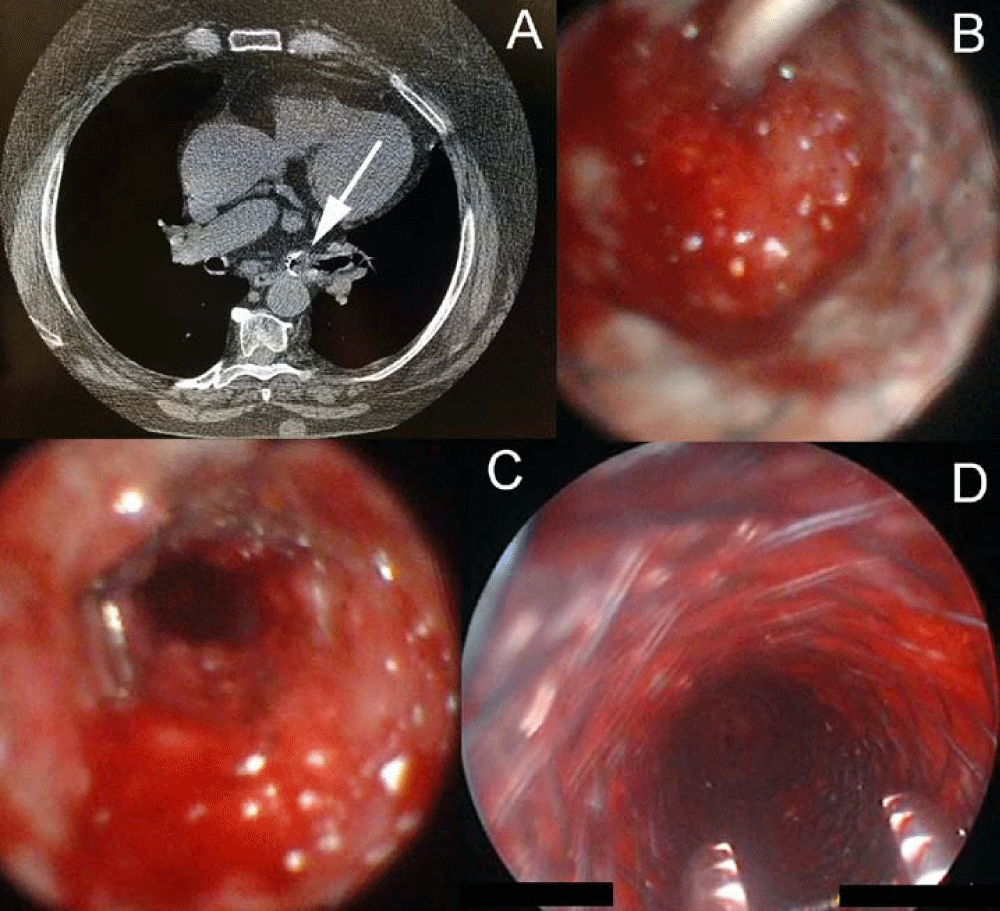

CT scan and emergency bronchoscopy revealed endobronchial mass obstructing the left and tracheal limbs of the Y shaped stent respectively (Figure 2A, 2B).

Two SEMSs were sequentially placed in left mainstem bronchus (Figure 2C) and trachea (Figure 2D) and recanalization of obstructed airway was obtained with improvement of symptoms.

Radiological evaluation Figure 3A, 3B showed the correct position of Y-Stent and of the additional two SEMSs with complete re-expansion of both lungs without sign of atelectasis. Nevertheless the patient died three months later from cardiac failure.